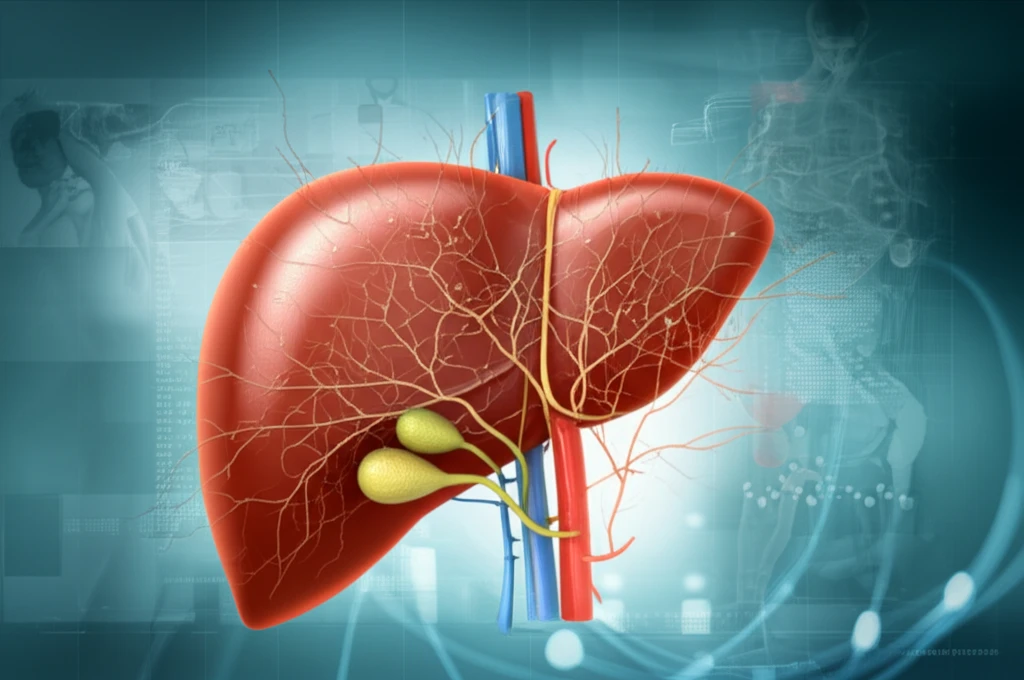

Our livers, the unsung heroes of our bodies, work tirelessly to filter toxins, produce essential proteins, and support overall health. But what happens when this vital organ faces chronic challenges? Recent studies reveal a concerning trend: hospitalizations related to chronic liver disease (CLD) are on the rise. This isn't just a matter of numbers; it's a reflection of how CLD is changing, affecting more people, and presenting new challenges for healthcare.

This article delves into the evolving landscape of CLD, examining the key findings of a population-based study that analyzed hospitalization trends. We'll explore the factors driving this increase, including the aging population, the rise of conditions like fatty liver disease, and the shift in complications from traditional issues like portal hypertension to modern challenges such as infections and renal failure. Understanding these trends is crucial for both healthcare professionals and individuals seeking to protect their liver health.